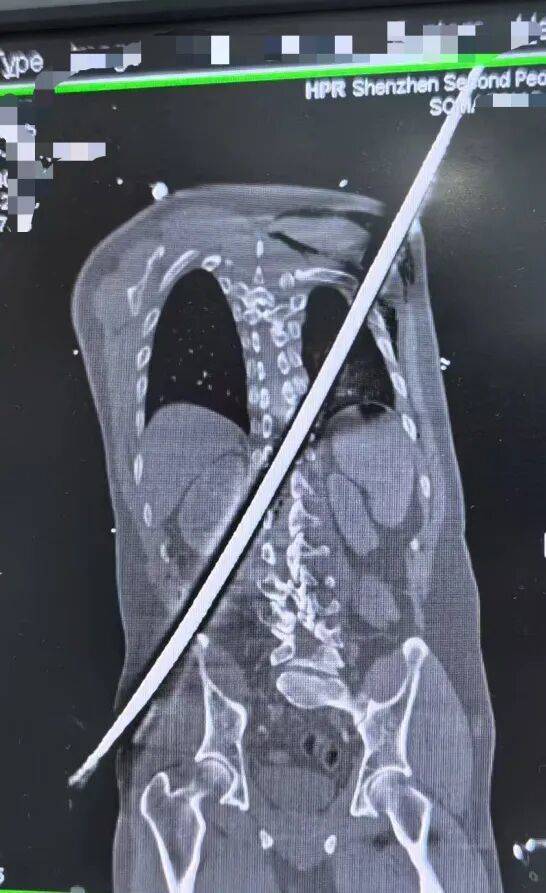

67厘米钢筋斜穿身体(ti)

据了解(jie),一场工地意外让男子(zi)遭遇(yu)了致命重创。一根细弱的钢筋,以67厘米的长度,从他右(you)侧臀部刺入,斜穿躯干,终究从左后侧肩背穿出(chu)。

被紧(jin)急送到深圳二院时,患者已(yi)经陷入休克,生命体(ti)征薄弱,随时大概离世(shi)。CT搜检更让医护人员倒吸(xi)一口冷气(qi):钢筋紧(jin)贴大血管、肾(shen)脏,击穿脊柱椎管,患者双下肢无法流动,稍有晃悠就大概引发瞬间大出(chu)血。

专家团队凭据CT影象精准(zhun)判断:钢筋穿行(xing)路径极(ji)度凶恶(e),犹(you)如正(zheng)在体(ti)内“走钢丝”,手术(shu)必需快、准(zhun)、稳,一旦失误就是致命风险。医院立即决定:立即手术(shu),全(quan)力一搏(bo)。